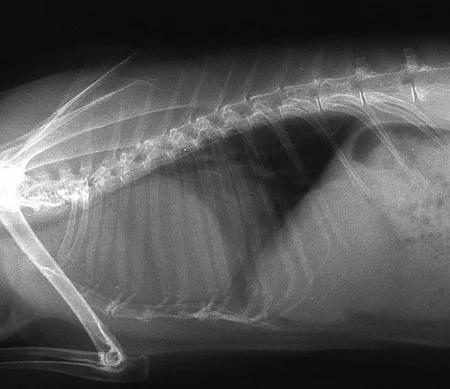

- Verdacht auf Fraktur (Abb. 1)